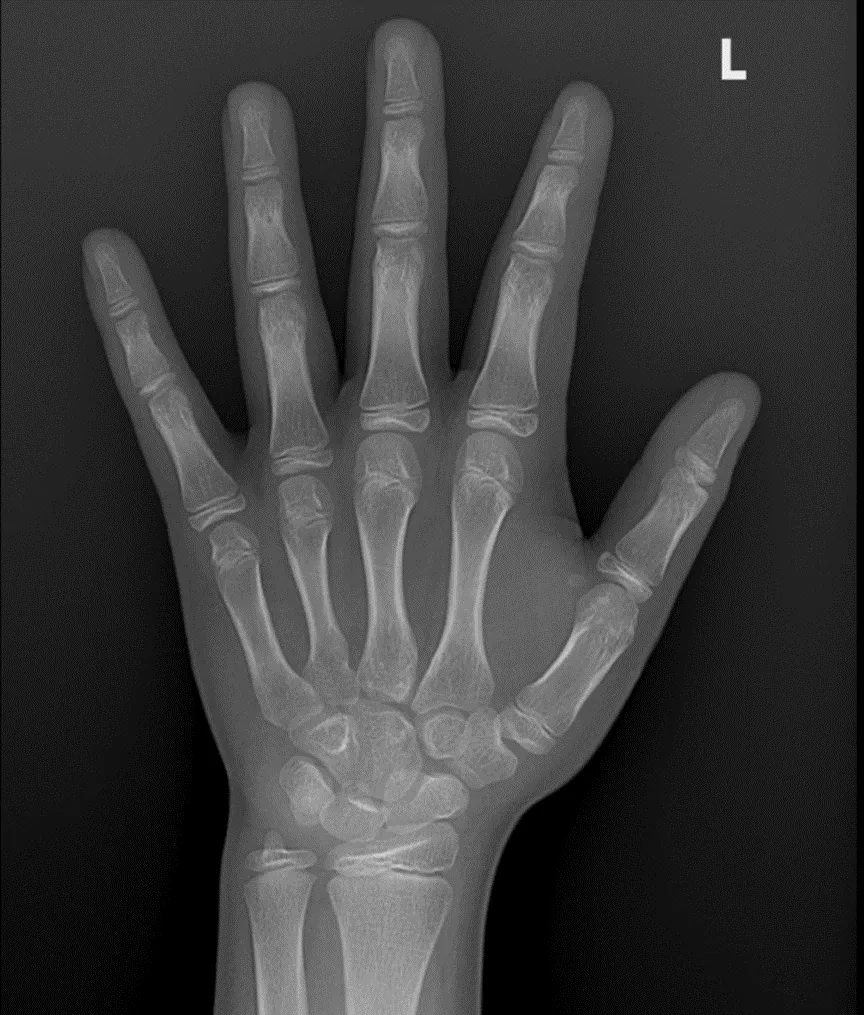

骨龄,即骨骼的年龄,是通过X光检查儿童的手腕、手掌或膝关节等部位的骨骼发育程度,评估其骨骼成熟度的“生物年龄”,它能反映骨骼的实际发育水平。

图为测试骨龄的腕关节X线图像